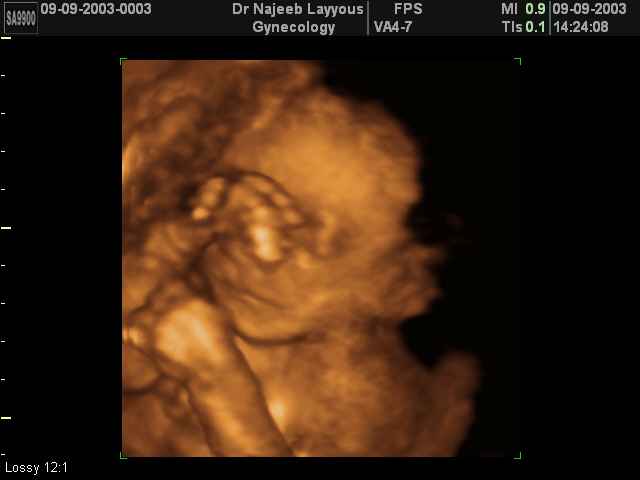

- Fetal Behavior Ultrasound Photos

Ultrasound Photos in 3D showing Fetal Behavior Inside the uterus | Dr N Layyous